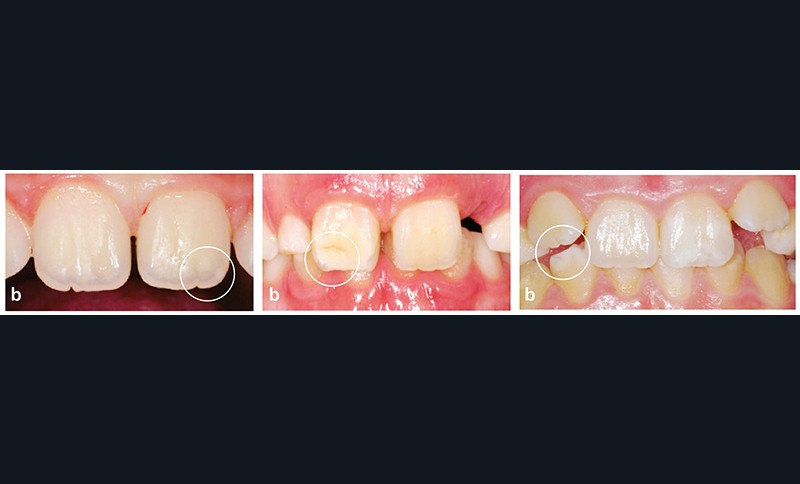

Comment la diagnostiquer ?

(fig. 1a à e)

• La MIH est une anomalie qualitative de l’émail.

• Elle touche au moins une première molaire permanente (PMP).

• Elle peut atteindre les incisives permanentes si une PMP est déjà atteinte.

• Les opacités sont bien délimitées, d’une couleur allant du blanc crémeux au jaune-brun au niveau des deux tiers

occlusaux ou des bords libres.

• Des fractures post-éruptives sont possibles.